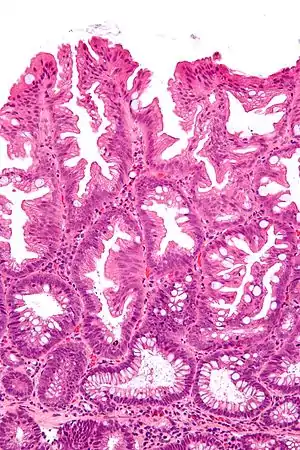

| Micrograph of a sessile serrated lesion. H&E stain. | |

SSLs are diagnosed by their microscopic appearance; histomorphologically, they are characterized by (1) basal dilation of the crypts, (2) basal crypt serration, (3) crypts that run horizontal to the basement membrane (horizontal crypts), and (4) crypt branching. The most common of these features is basal dilation of the crypts.

Unlike conventional colonic adenomas (e.g. tubular adenoma, villous adenoma), they do not (typically) have nuclear changes (nuclear hyperchromatism, nuclear crowding, elliptical/cigar-shaped nuclei).